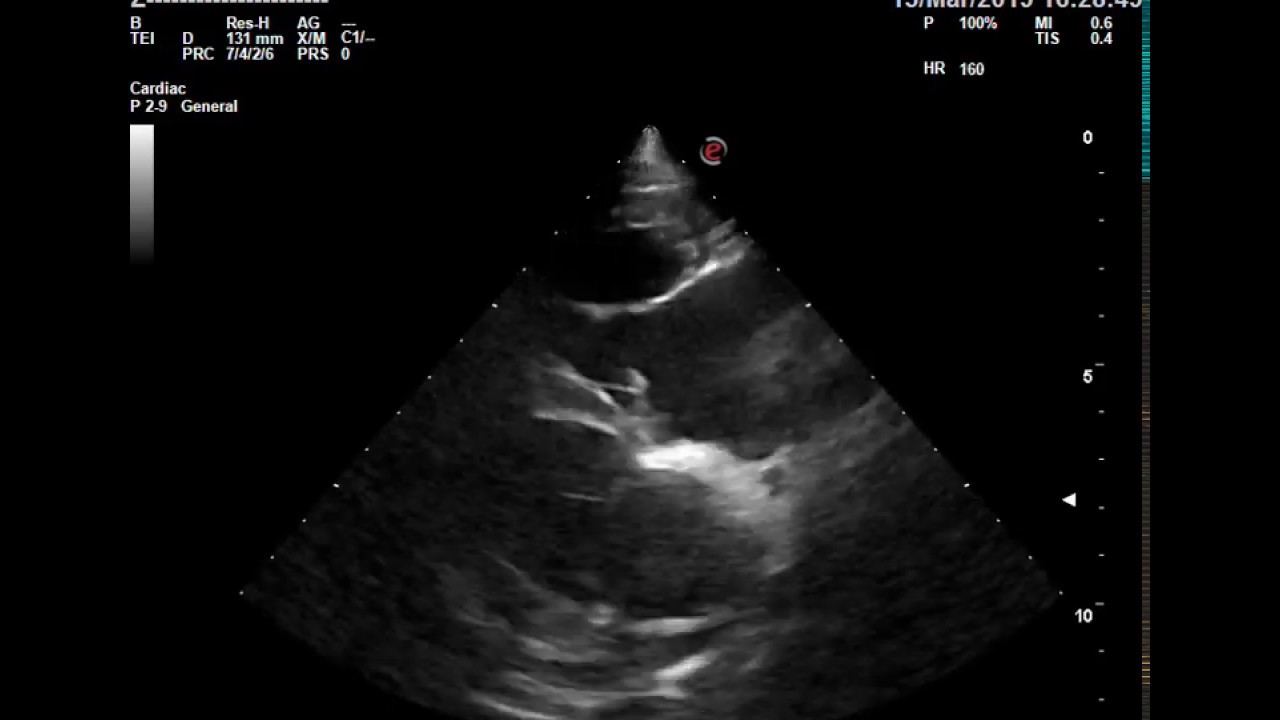

Echo serca płodu (echokardiografia) Gyncentrum